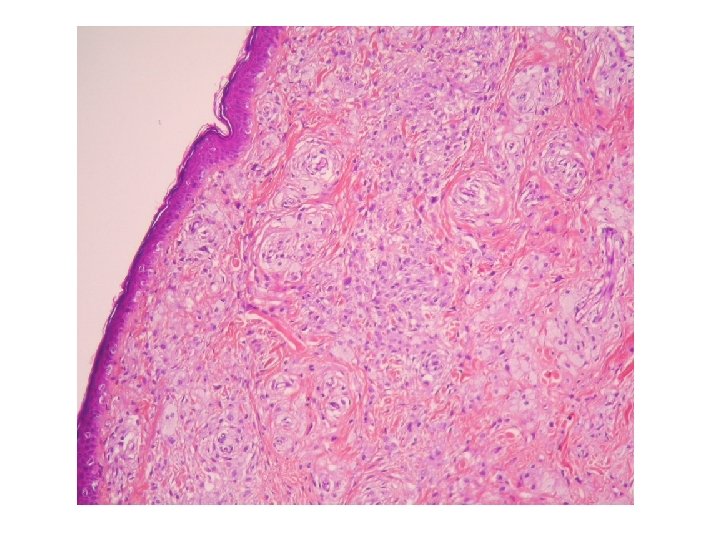

Prélevement cutané avec des lésions pseudo tumorales. epiderme

En profondeur du derme on retrouve le granulome. Au contact des particules blanches (corps

En profondeur du derme on retrouve le granulome. Au contact des particules blanches (corps étrangers), on retrouve des éléments faisant penser à plus fort grossissement que les corps étrangers ont été phagocytés par des macrophages.